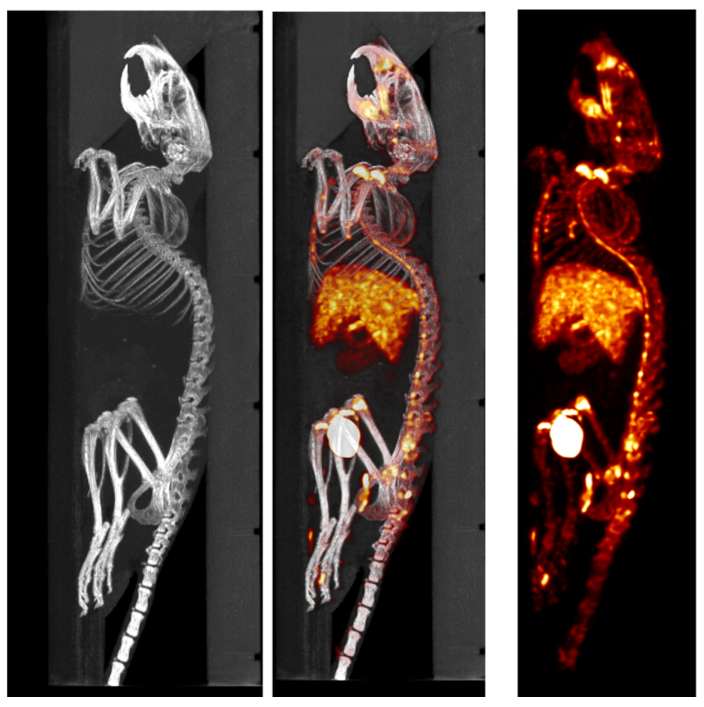

SPECT/CT組合圖像,小鼠的骨骼成像:99mTc-HDP,94.35MBq (2.55mCi) @ start acquisition,采集時間60min。

SPECT/CT組合圖像,大鼠的骨骼成像:99mTc-HDP,200MBq,采集時間45min。